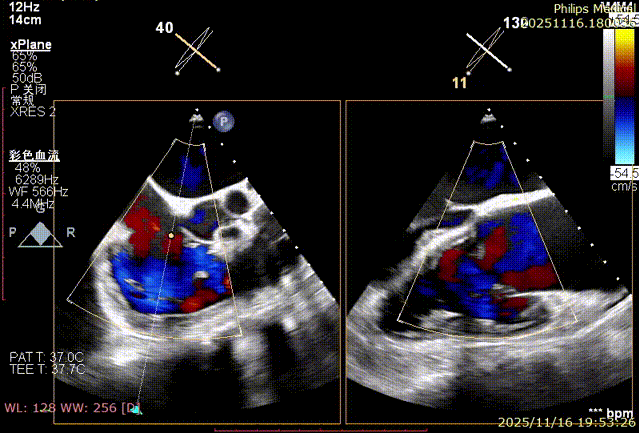

Echocardiographic Assessment: Echocardiography revealed left atrial enlargement. The left atrial appendage (LAA) orifice was 32mm with no thrombus inside. Tricuspid regurgitation was extreme (average vena contracta 18mm). Regurgitant jets were located at the anterior-septal, central, and posterior-septal commissures, with a central gap measuring approximately 13x5.9mm. The annulus was mildly dilated (average diameter 43mm). The tricuspid leaflets showed thickening and degenerative changes.

Immediate intraoperative echocardiographic verification showed that the tricuspid regurgitation area was significantly reduced from a preoperative grade of 5+(pre-op) to 2+(post-op), downgrading the severity from extreme to mild-moderate.

Comparison of TR regurgitation severity: reduced from 5+ to 2+

- TR Severity Comparison: Reduced from 5+ to 2+.